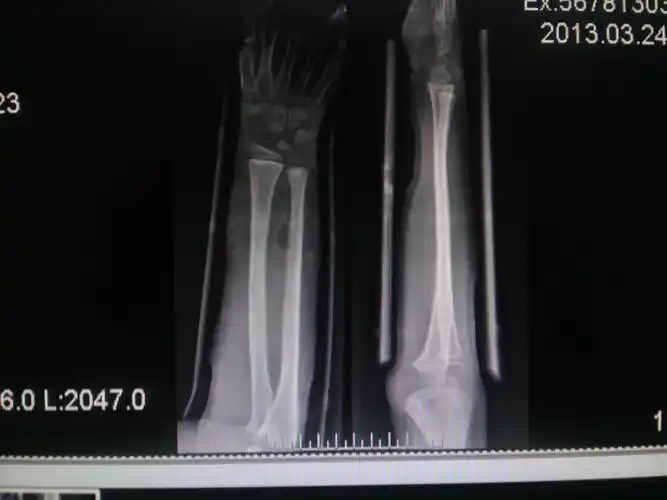

左尺桡骨折青枝骨折

小儿青枝骨折 [病例帖]

病例讨论成人青枝骨折